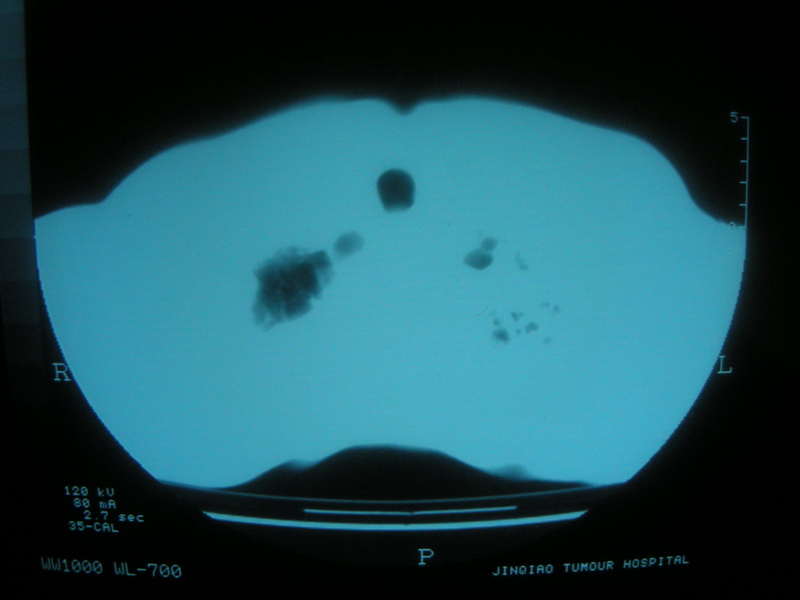

标题: CT11692:男,63岁,糖尿病史15年.抗炎治疗7天,病情 [打印本页]

标题: CT11692:男,63岁,糖尿病史15年.抗炎治疗7天,病情

请老师看看是结核还是炎症?

根据影像表现及临床符合结核感染。

双肺继发性肺结核伴感染!